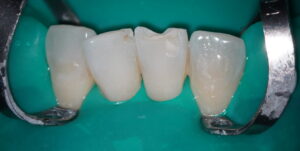

ダイレクトボンディングをされた患者様の紹介です。下顎の前歯部の破折を主訴に来院されました。

ダイレクトボンディングをする上でラバーダム防湿は必須のアイテムでしょう。コンポジットレジン修復において水分は大の敵です。いかに隔離して、乾燥できるかがポイントです。

防湿ができたら、表面を清掃し酸処理を行います。

エッチングによって表面を粗造にしていきます。表面積も広がり、コンポジットレジンがより強固に浸潤・接着します。